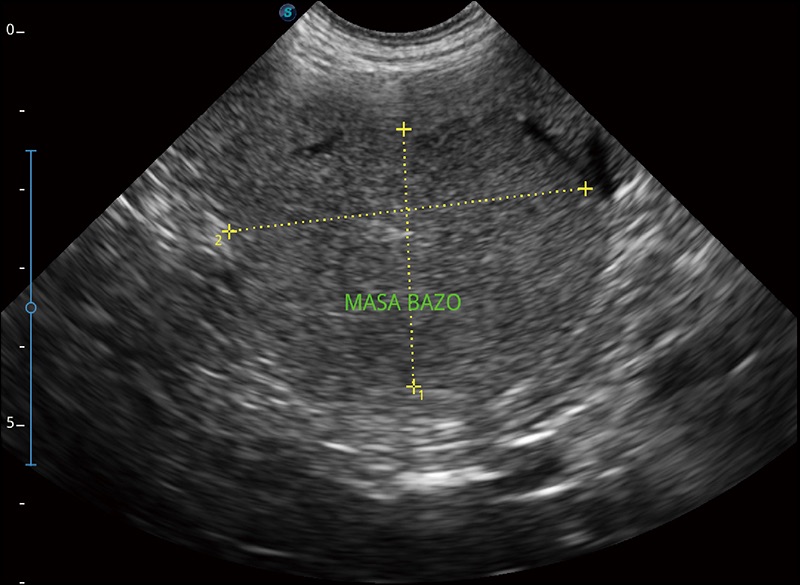

α1卓越的圖像質(zhì)量和便捷的工作流程,使每位寵物醫(yī)生都能輕松掃查。其全面的獸用應(yīng)用功能和緊湊型的結(jié)構(gòu)設(shè)計(jì),可以滿足動(dòng)物檢查的多種需要。專(zhuān)業(yè)的預(yù)設(shè)檢查模式和多領(lǐng)域測(cè)量軟件包有助于為不同類(lèi)型的動(dòng)物提供檢查, 讓寵物醫(yī)生能夠出色的完成工作。